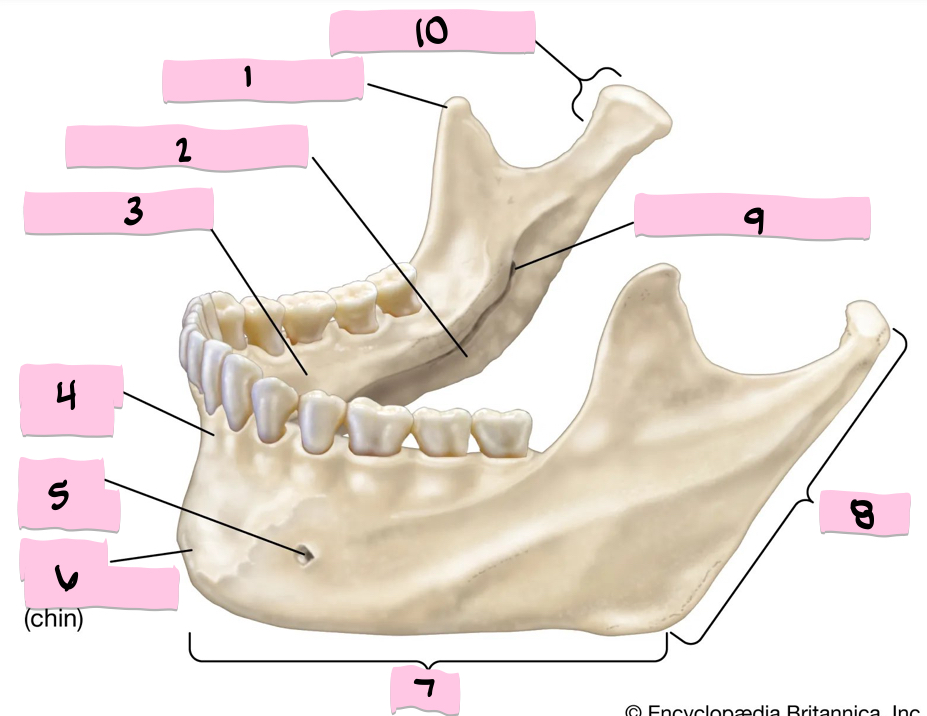

What is 1 pointing to?

Coronoid process

What is 2 pointing to?

Submandibular fossa

What is 3 pointing to?

Sublingual fossa

What is 4 pointing to?

Alveolar process

What is 5 pointing to?

Mental foramen

What is 6 pointing to?

Mental protuberance

What is 7 pointing to?

Body

What is 8 pointing to?

Ramus

What is 9 pointing to?

Mandibular foramen

What is 10 pointing to?

Condylar process